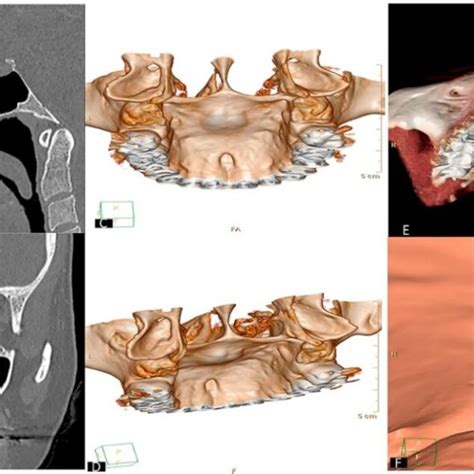

- Consumo de cocaína: El contacto de la cocaína con las mucosas causa una vasoconstricción y la subsecuente necrosis de la mucosa y los tejidos de sostén (cartílago y hueso). El contacto frecuente y repetitivo causa la destrucción y perforación del tabique medio nasal, las coanas, las paredes de los senos paranasales y la bóveda palatina.

En las lesiones ulcerativas que afectan la línea media de la cara se deben de considerar dentro de los diagnósticos diferenciales varias lesiones, en las que se encuentran las de etiología traumática, infecciosas y neoplásicas, tales como la granulomatosis de Wegener, linfoma de células T/NK de tipo nasal y la mucormicosis, entre otras; el rinoescleroma y algunos otros linfomas, deberán también tomarse en cuenta, aunque son raros.

- Granulomatosis de Wegener: es una lesión granulomatosa necrosante, poco frecuente, que inicia con ulceración granulomatosa del tracto respiratorio, la cual en algunos pacientes va acompañada de gromerulonefritis, mientras que otros pacientes solo presentan las lesiones en vías aéreas sin afección renal.

- Linfoma de células T/NK de tipo nasal: es otro diagnóstico que se debe considerar en este tipo de lesiones; este linfoma es más común en la población asiática y en zonas de Latinoamérica como Perú, Guatemala y México, en donde se le ha asociado al Virus Epstein-Barr.

- Mucormicosis: es otro de los diagnósticos a considerar, este es causado por un hongo oportunista, saprofito, cuando afecta la cavidad oral es la forma rinocerebral.